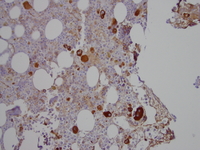

Factor VIIIvw immunohistochemistry stain

Factor VIIIvw immunohistochemistry stain highlights atypical megakaryocytes showing range in size with small mononuclear forms.

Refractory-cytopenia-of-childhood-GATA2-deficiency-related-Factor-VIIIvw-immunohistochemistry-stain

#00060447